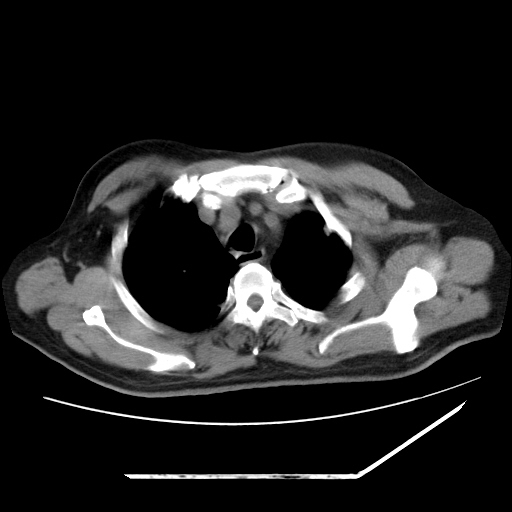

男,57,畏寒,发热

两肺野多发大小不一高密度灶,纵膈内见肿大淋巴结,要考虑转移瘤可能。双侧胸腔少量积液。

双肺多发结节样病灶,部分内见透光区,纵隔内见淋巴结肿大。结核临床如有畏寒,高热,白细胞增高首先考虑迁徙性肺脓肿(多是金黄色葡萄球菌感染)。

注意除外转移瘤。

1)考虑两肺感染性病变(金黄色葡萄球菌肺炎?);建议抗炎治疗后复查排除其他。2)双侧少量胸腔积液。